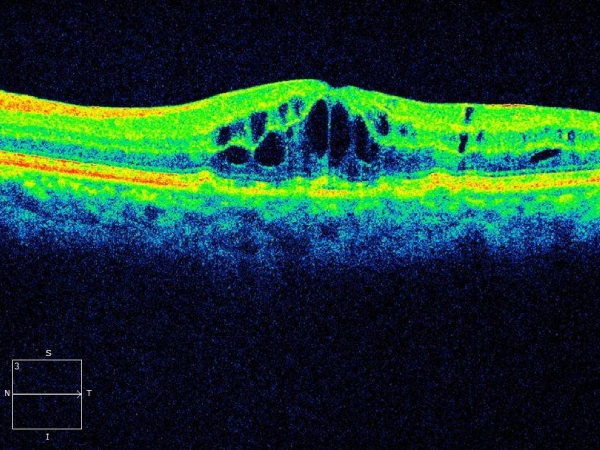

Diabetic retinopathy with clinically significant macular edema requires

• Strict diabetes control

• Combination of grid laser photocoagulation and intravitreal injection of an anti vegf antibody/sustained release steroid implant

In a poorly controlled diabetic who has not been screened for diabetic retinopathy Plaques of yellow cholesterol accumulation under the macula with severe retinal swelling will cause gross irreversible visual loss You need an eye check up with retinopathy screening tests within one year of detection of diabetes